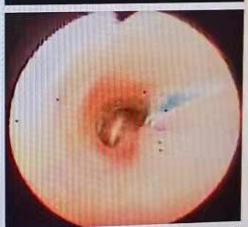

程医生为孩子联系了内镜,内镜中心副主任医师利奥为孩子做了内镜检查。这次调查发现了这个秘密。造影剂被注射到食道,但也在支气管中发现,这意味着食道和支气管之间应该有一个“秘密通道”。

内窥镜检查显示显影剂漏入支气管。

“秘密通道”在哪里?随着内镜的不断探索,我们终于找到了问题的症结:——“秘密通道”位于食管、支气管中上部,是一个直径约1毫米的小孔。.

这个小洞的存在导致小乖乖食道里的牛奶和食物“漏”进支气管,引起呛咳,继而引发肺炎。